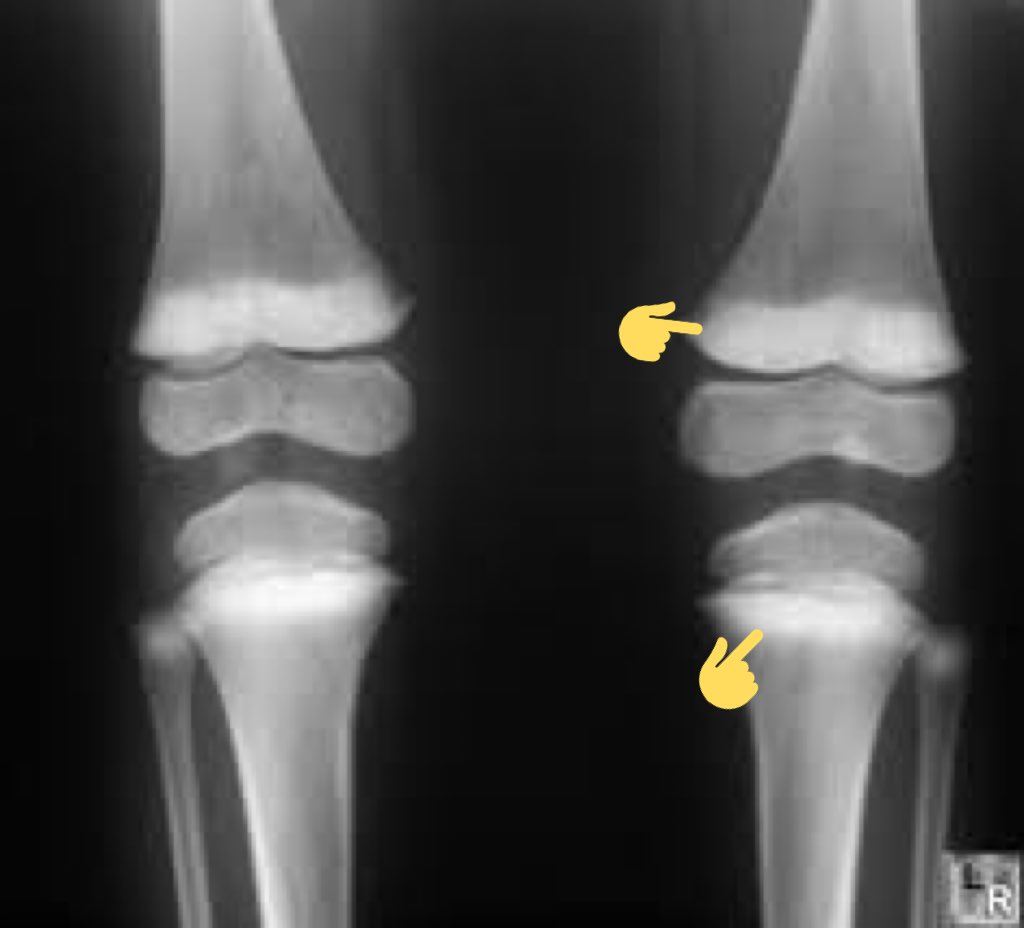

🦴 #تقوس "ميلان" السيقان:

هل تعلم بأن التقوس إلى الداخل يحدث بشكل طبيعي عند الرضيع و حتى ١٨ شهر، ومن ثم تبدأ الأرجل في الاستقامة عند سن الثانية.

يبدأ الميلان الى الخارج عند عمر ٣-٤ سنوات "تلاصق الركبتين" حتى تصل إلى الشكل الطبيعي عند سن السابعة كما هو موضح بالصورة المرفقة👇🏼.

• مرض #بلاونت:

و فيه تتطور ساق الطفل بشكل غير طبيعي، وتنحني أسفل الركبتين، و عندما يبدأ طفلك في المشي، يصبح انحناء الساقين أسوأ.

قد تكون هذه الحالة واضحة في وقت مبكر، ولكن في بعض الحالات قد لا تكون الأعراض ملحوظة حتى يبلغ الطفل سن المراهقة.

🔎 التشخيص:

-⚠️ الأشعة السينية أو غيرها لعرض أي تشوهات عظمية في ساقيك وركبتيك.